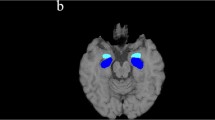

In a previous study [7], investigating brain tissue integrity by means of voxel-based morphometry (VBM) and T1-weighted/T2-weighted (T1w/T2w) maps, a whole-brain voxel-level analysis revealed reduced volume in bilateral putamen and cerebellar gray matter (GM), reduced white matter (WM) volume in the cerebellum and brainstem, and increased mean regional values of T1w/T2w in bilateral putamen in MSA patients compared to both Parkinson’s disease (PD) patients and healthy controls (HC). Specifically, the ratio of the signal intensity of the T1-weighted and T2-weighted (T1w / T2w) MRI images has been used as semi-quantitative measure for myelin content in gray matter and its advantage that images with high spatial resolution can be easily acquired without complex modeling, during routine clinical examination [7].

Regional mean values of each parameter (GM, WM and T1w/T2w) at each time point were calculated in each cluster binary masks obtained in the voxel-level analysis of our previous study [7] performed on the baseline data. Particularly, regional cluster values in bilateral putamen, cerebellar GM, and cerebellar/brainstem WM were considered as region of interest in the present study.

Logistic regression analysis showed that age (β = − 9.45, p = 0.02) and T1w/T2w value in the Left putamen (β = 230.64, p = 0.01) were significant predictors of global cognitive status at T0, explaining 65% of the variance (R2 = 0.65).